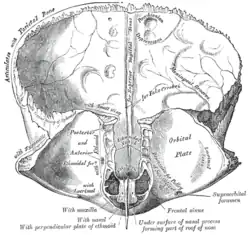

Left parietal bone. Inner surface. Frontal bone. Inner surface.

On the inner surface of cranial bones, small pits called granular fovea are produced by arachnoid granulations.[3][4]